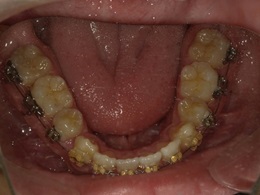

治療前下顎

治療中下顎

治療後下顎